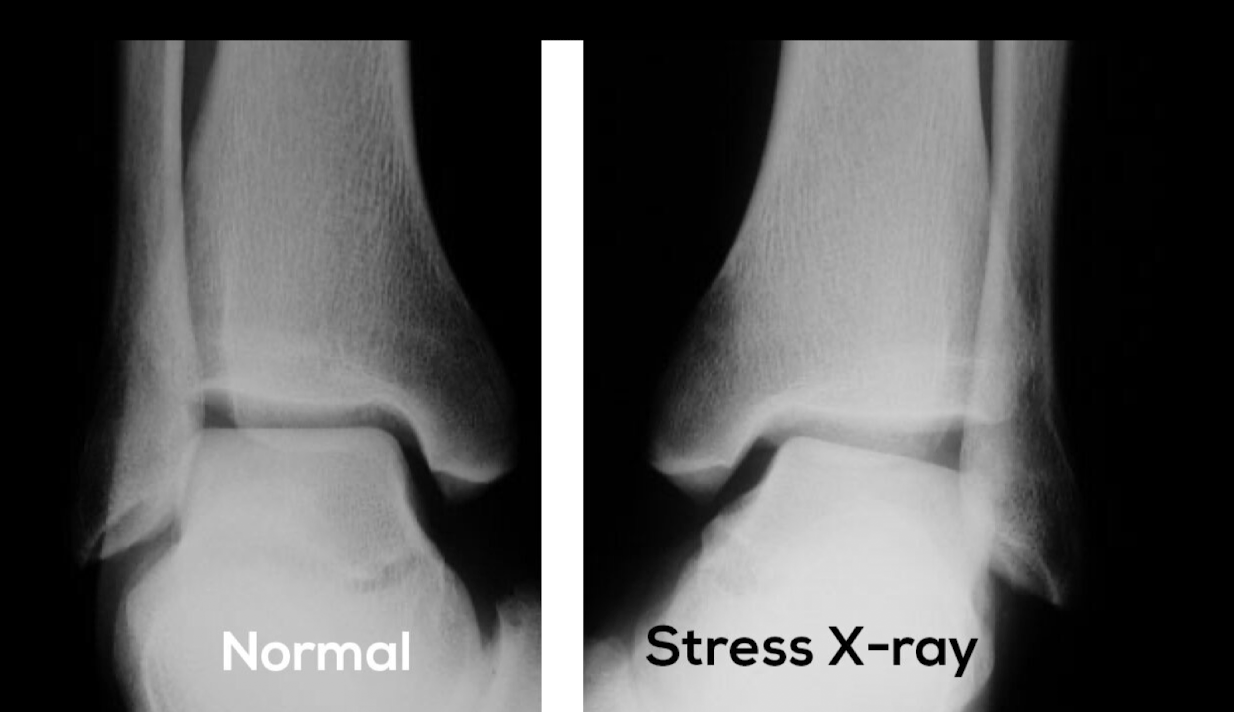

Q

RX estrés

A

RX ESG

NO ve el lig: SI datos secund

- Edema tx blandos

- aumento del espacio entre peroné y ástragalo

Rx con estrés “bostezo”

- Descartar fx

TC usualmente para buscar fracturas